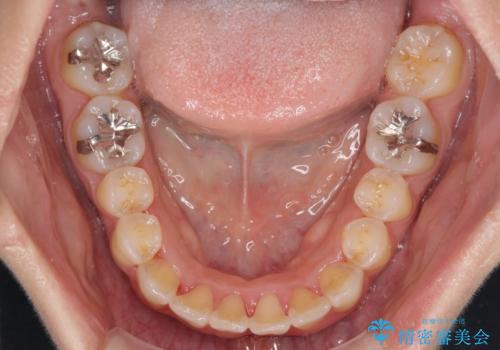

前歯のデコボコをインビザラインでスッキリと

- 上下前歯のデコボコを気にして来院された患者様です。

デコボコを解消する過程で、歯列の拡大により口元が突出する可能性があったため、4本の親知らずを抜歯しておき、歯列全体が後方に移動するように設計し、インビザラインにて矯正治療を行うこととしました。

日々の装着時間をしっかりと守って治療の臨んでくださったため、治療前のシミュレーションに近い形で矯正治療を進めて行くことができました。